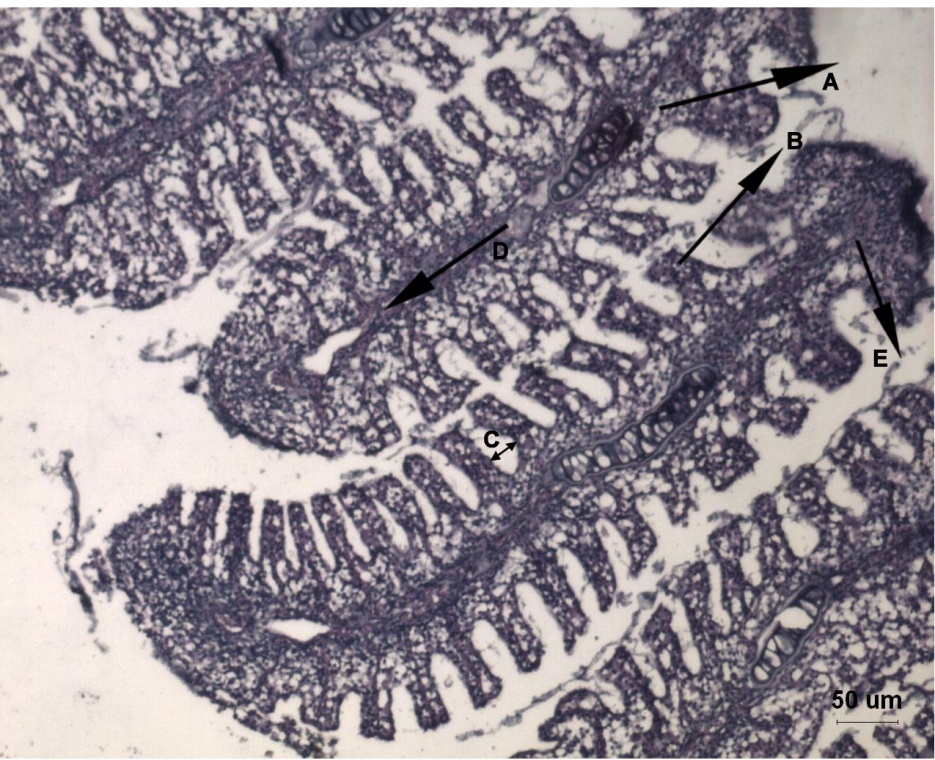

Fig. 4: Histological alterations of gills of Labeo rohita fish exposed to lead acetate and fed with normal fish food supplemented Hydrilla verticillata stained with Hematoxylin and Eosin showing normal architecture. A-Primary Lamellae (PL), B-Secondary Lamellae (SL), C-Inter Lamellar Space (ILS), D-Cartiligous Rod, E-Primary Epithelium (PE). Scale Bar = 50 µm

The gill of lead acetate exposed fish, fed with normal food (fig. 1b & fig. 1c) showed remarkable histopathological lesions like thickening of the supporting cartilaginous rods and hyperplasia of the epithelial cells that caused fusion of adjacent secondary gill lamellae. In addition, the secondary lamellae became shorter and lamellar fusion formed lumps. Further, edema between the primary epithelium and secondary lamella, severe degeneration with fibrosis in primary filaments and disappearance of inter lamellar spaces (ILS), were also observed. The gill of lead acetate exposed fish fed with supplementary food (fig. 1d) expressed apparently normal architecture of control fish.